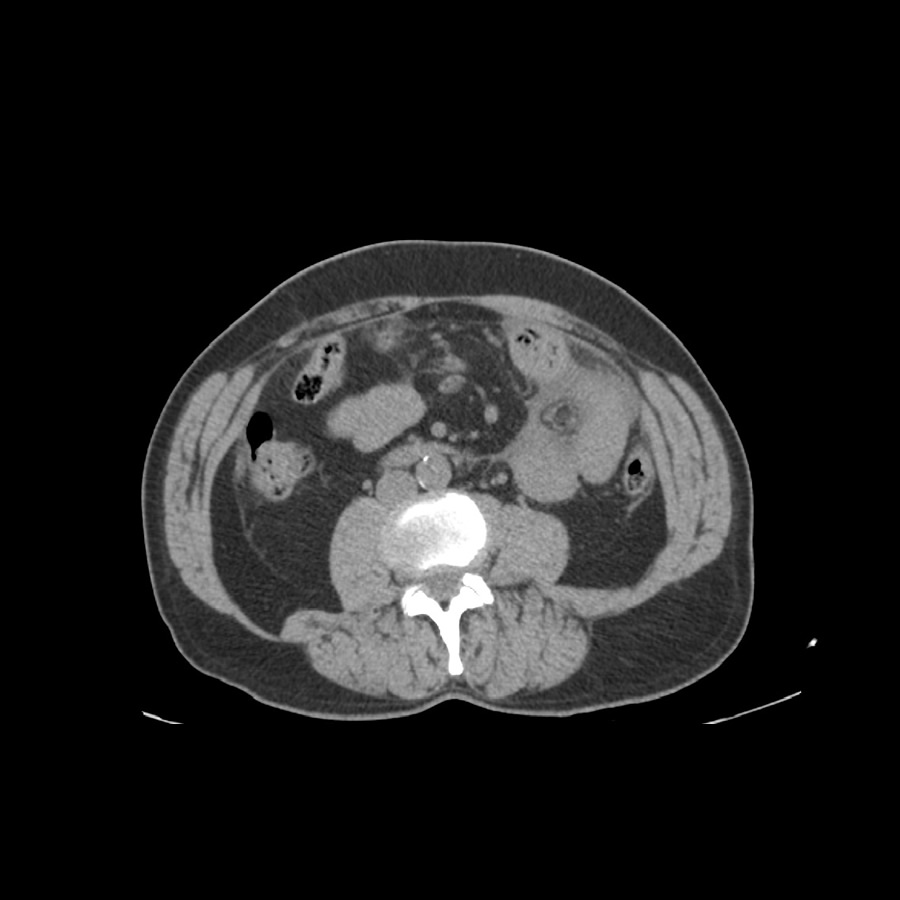

Paciente masculino de 57 años, dolor abdominal. AEA: Traumatismo